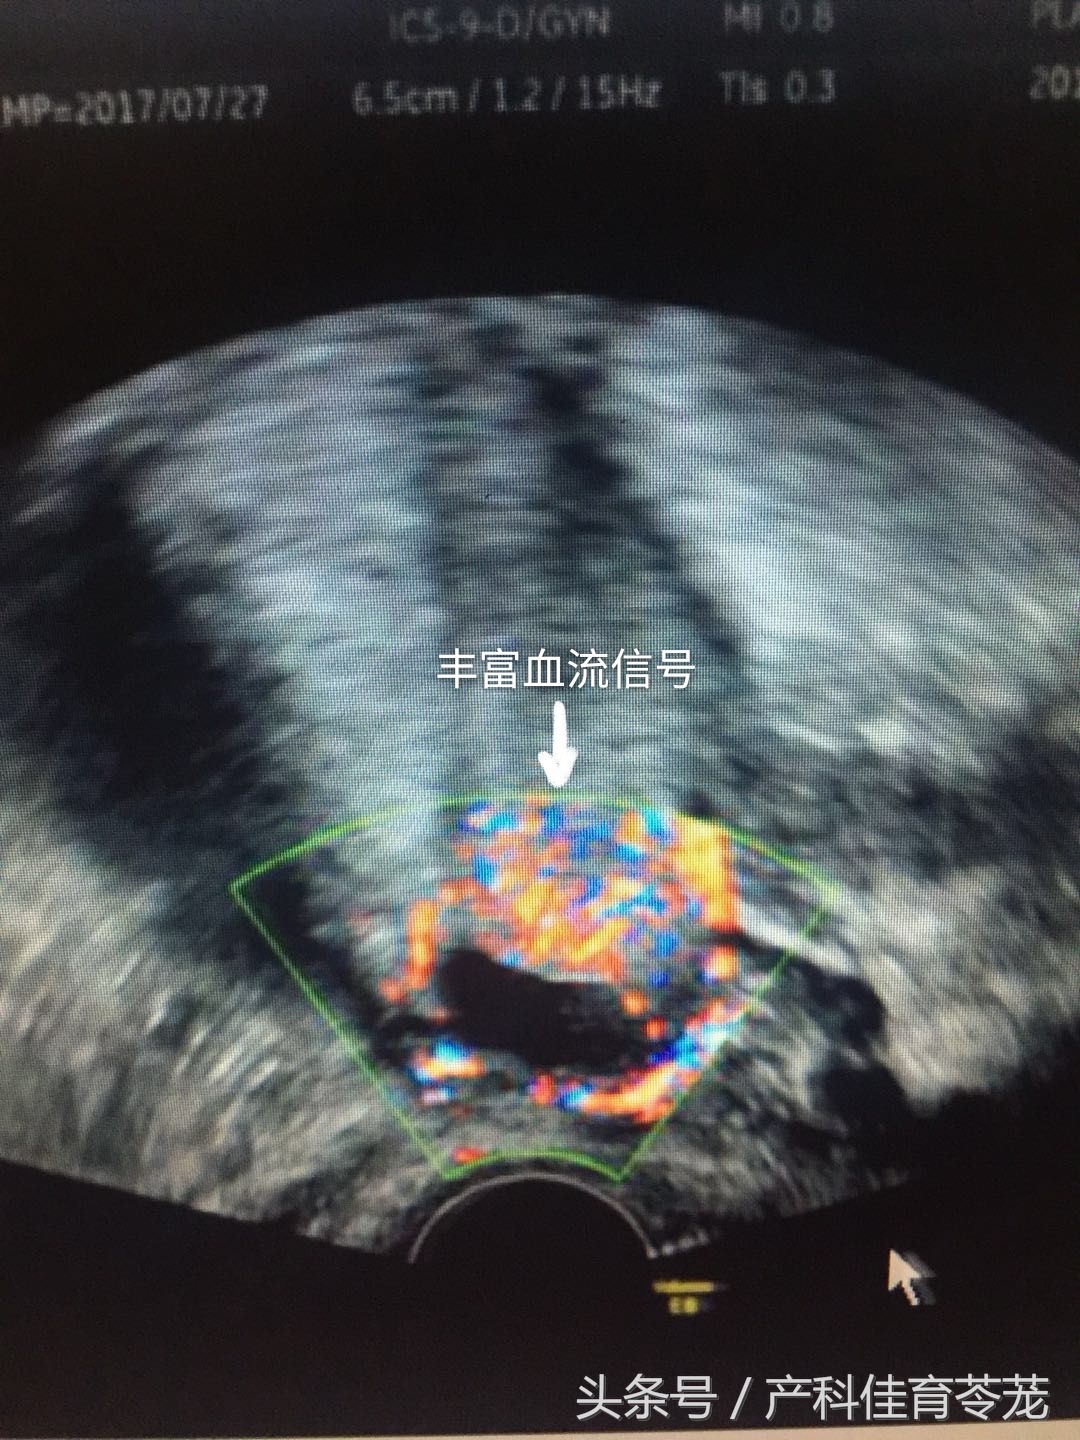

做了B超检查是这样的:

诊断为“瘢痕妊娠”,在腹腔镜监视下做了妊娠物清除术。

彩色多普勒血流显像(CDFI)显示孕囊周边高速低阻血流信号;